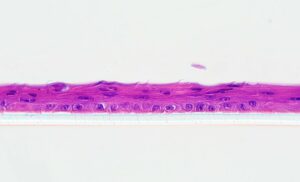

The European Centre for the Validation of Alternative Methods (ECVAM) เป็นองค์กรกลางของสหภาพยุโรป ทำหน้าที่ประเมินและตรวจสอบความใช้ได้ของวิธีทางเลือกทดแทนการใช้สัตว์ทดลอง ปัจจุบันมีวิธีทดสอบทดแทนการใช้สัตว์ทดลอง (Alternative methods) ที่ได้รับการรับรองและได้รับการบรรจุเข้าใน test guideline (TG) ของ Organization for Economic Co-operation and Development (OECD) สำหรับการทดสอบความปลอดภัยด้านต่างๆ ได้แก่ การใช้แบบจำลองผิวหนังชั้นนอกในการทดสอบฤทธิ์กัดกร่อนผิวหนัง (OECD TG 431) และการระคายเคืองต่อผิวหนัง (OECD TG 439) และการใช้แบบจำลองเยื่อบุดวงตาในการทดสอบการระคายเคืองต่อดวงตา (OECD TG 492) เป็นต้น วิธีเหล่านี้ต้องอาศัยแบบจำลองของเนื้อเยื่อเป้าหมายที่สร้างขึ้นจากเซลล์หรือเนื้อเยื่อของมนุษย์ ทำให้มีลักษณะโครงสร้างเป็นแบบสามมิติ (3D) ที่มีความคล้ายคลึงกับเนื้อเยื่อจริงทั้งทางด้านกายภาพและการตอบสนองทางชีวภาพ

สวทช. ได้มีการนำเนื้อเยื่อจำลองของผิวหนังชั้นนอก (Reconstructed human Epidermis; RhE) ที่ผ่านการยอมรับโดย ECVAM เปิดให้บริการทดสอบผลิตภัณฑ์ตั้งแต่ปี พ.ศ. 2553 ซึ่งถือเป็นแห่งแรกในประเทศไทย ด้วยเล็งเห็นว่าวิธีทางเลือกที่ทดแทนการใช้สัตว์ทดลองนี้เป็นสิ่งที่ท้าทาย และจะเป็นประโยชน์ต่อประเทศไทยในอนาคต